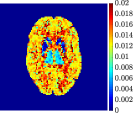

Figure 4, Figure 5, and Figure 6 show the mean images computed over the ten reconstructions obtained by the methods reg-AS-TR, reg-GN, and by the Matlab routine lsqcurvefit implementing a standard Trust-Region-Reflective least-squares algorithm [11, 10]. We used the noise-free IF and the perturbed IF with and of noise, respectively. Figure 7 contains mean and standard deviation values of the kinetic parameters computed over the ten reconstructions and over each one of the four homogeneous regions, for each one of the three noise levels on the IF.

In general, reg-AS-TR and lsqcurvefit seem to provide similar mean reconstructions, although uncertainties associated to lsqcurvefit are significantly bigger. On the other hand reg-GN seems to systematically underestimate the parameter values within region . Furthermore and as expected, for all methods the quality of the parametric reconstructions deteriorates with increasing noise levels; this is more clear from the and parametric images, probably due to the different sensitivities of the data with respect to the model parameters [37]. In reg-GN and lsqcurvefit some artifacts can be observed at the edges of the homogeneous regions, especially around region and region , whereas the effect of regularization in reg-AS-TR results in a reduced presence of artifacts while the structure of the regions is preserved. This general trend is confirmed by the error-bar plots of Figure 7. Finally, the frames in Figure 8 corresponding to reg-AS-TR show a significant improvement of the image quality with respect to what is provided by the other two approaches.